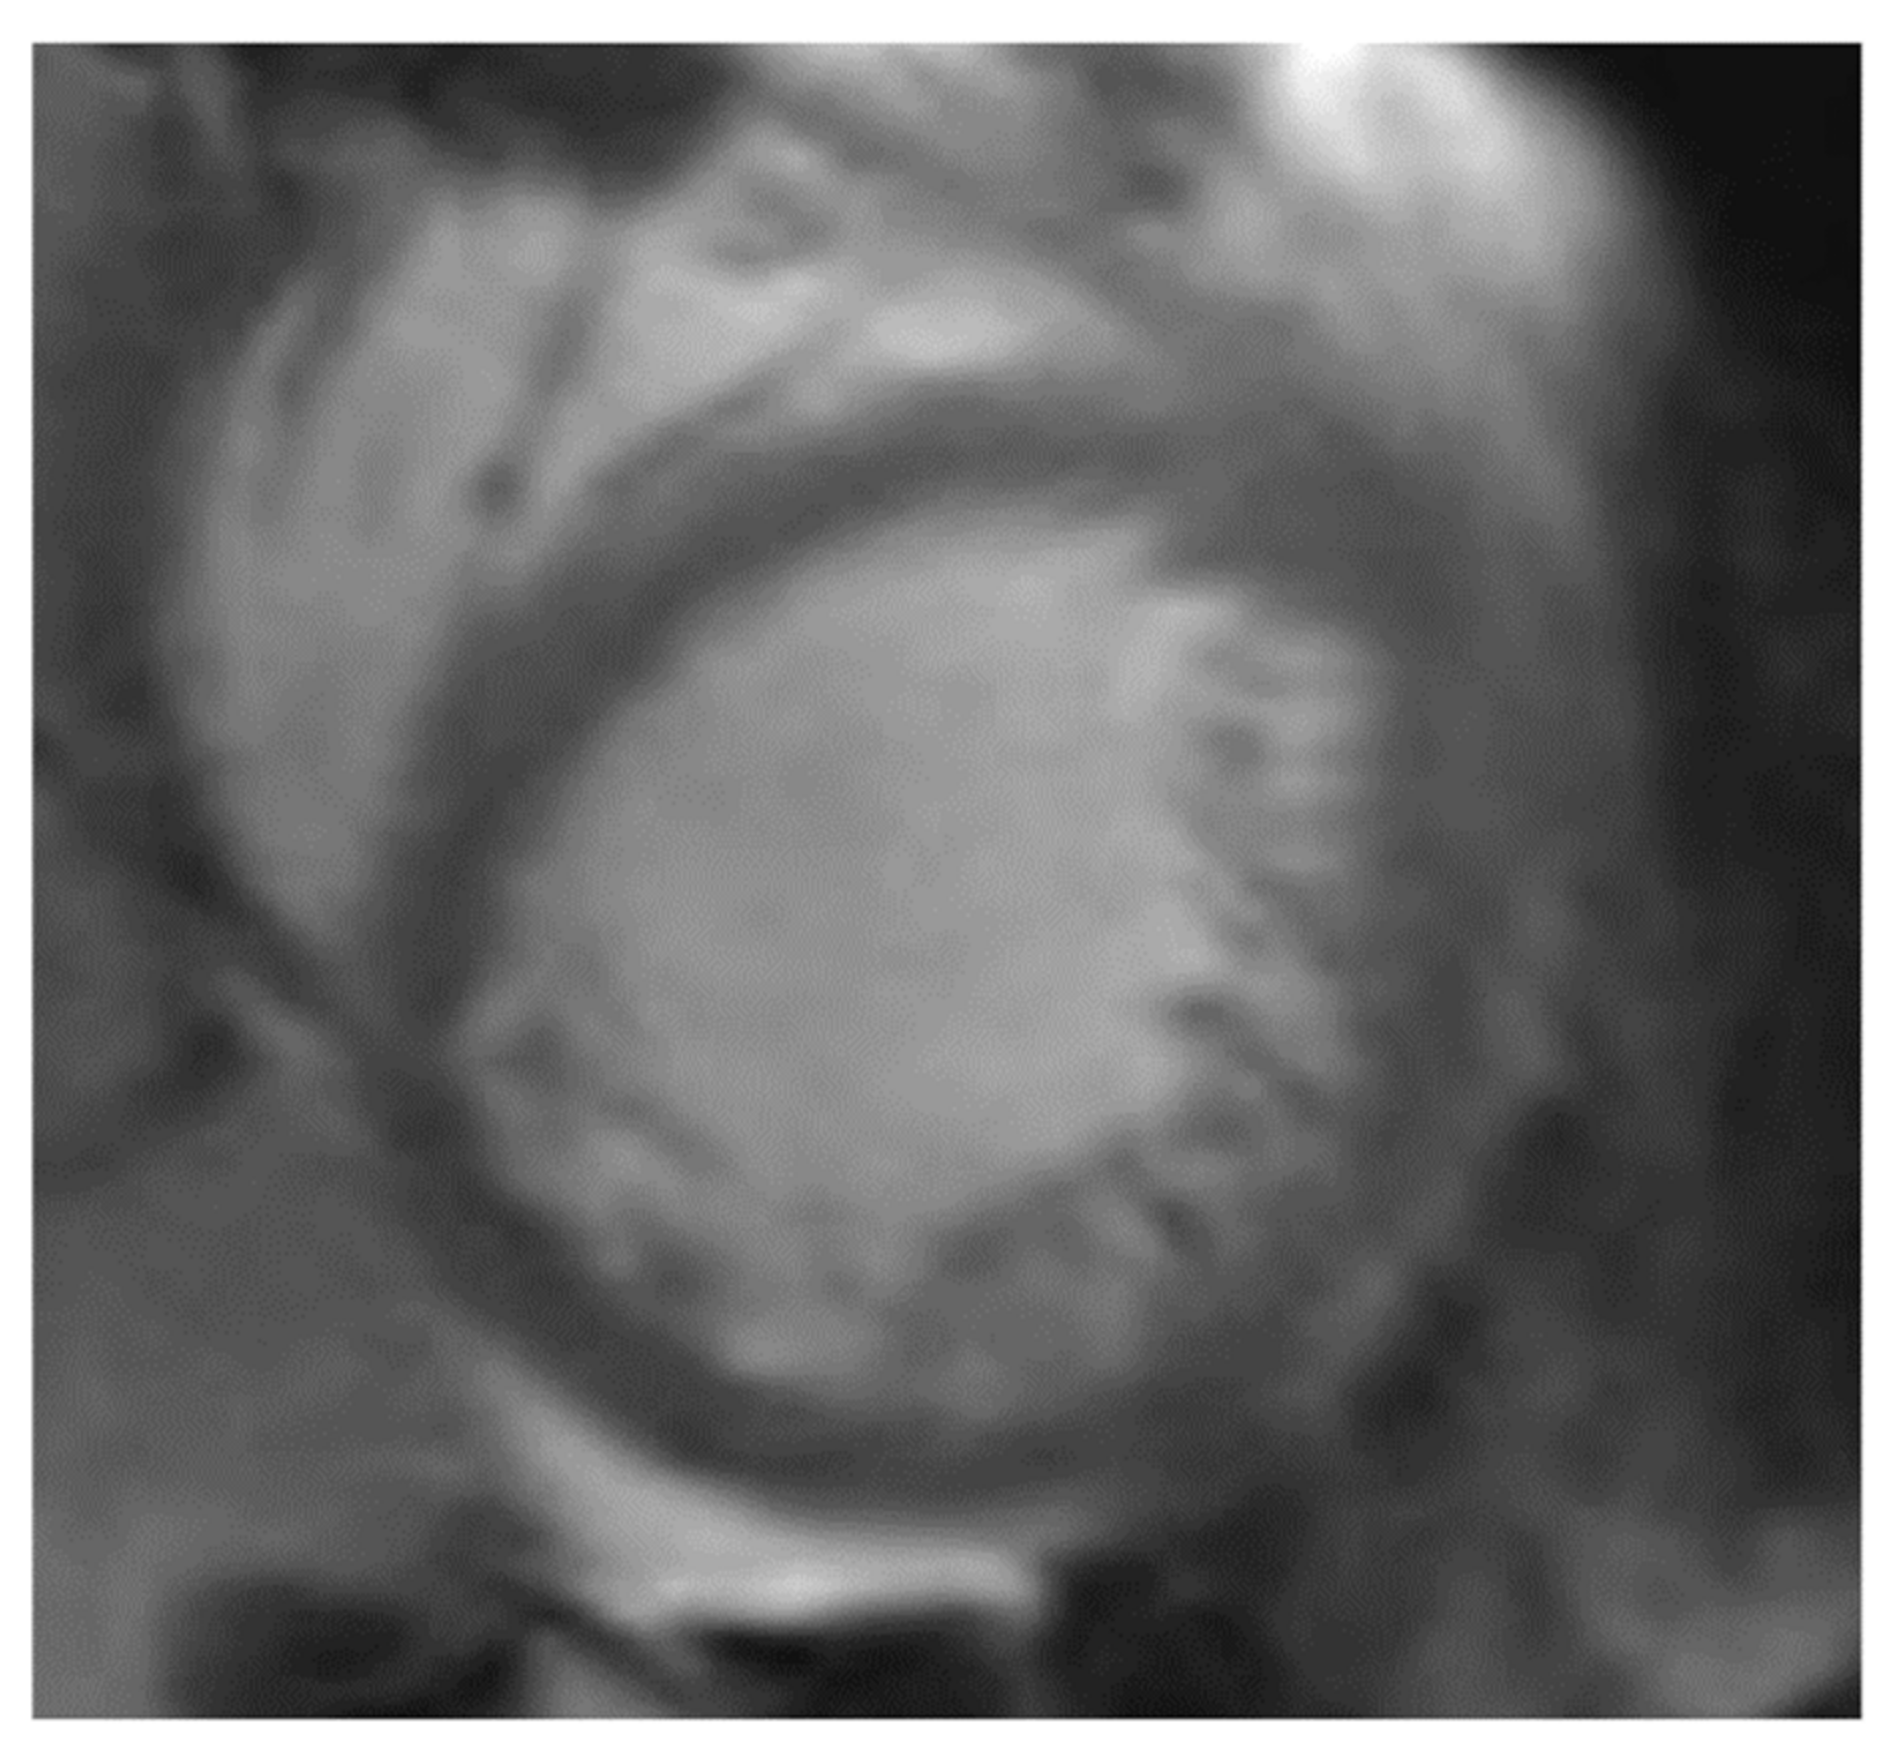

- Petersen, S.E.; Selvanayagam, J.B.; Wiesmann, F.; Robson, M.D.; Francis, J.M.; Anderson, R.H.; Watkins, H.; Neubauer, S. Left Ventricular Non-Compaction. Insights from cardiovascular magnetic resonance imaging. J. Am. Coll. Cardiol. 2005, 46, 101–105. [Google Scholar] [CrossRef] [PubMed]

- Stacey, R.B.; Andersen, M.M.; Clair, M.S.; Hundley, W.G.; Thohan, V. Comparison of Systolic and Diastolic Criteria for Isolated LV Noncompaction in CMR. JACC Cardiovasc. Imaging 2013, 6, 931–940. [Google Scholar] [CrossRef] [PubMed]

- Jacquier, A.; Thuny, F.; Jop, B.; Giorgi, R.; Cohen, F.; Gaubert, J.-Y.; Vidal, V.; Bartoli, J.M.; Habib, G.; Moulin, G. Measurement of trabeculated left ventricular mass using cardiac magnetic resonance imaging in the diagnosis of left ventricular non-compaction. Eur. Heart J. 2010, 31, 1098–1104. [Google Scholar] [CrossRef]

| Petersen 2005; [85] | Trabecular layering | Compacted epicardial and noncompacted endocardial layer | NC/C > 2.3 | True apex excluded | End diastole | Long axis | |

| Jacquier 2010; [87] | Trabeculated LV mass | Perfused, deep recesses | Jenni echo criteria | Trabeculated mass > 20% | End diastole | Short axis | |

| Stacey 2012; [86] | Trabeculation | Flow in the recesses | Noncompacted and compacted layer | NC/C > 2.0 | 16–24 mm from the true apex | End systole | Short axis |

| Captur 2015; [88] | Abnormal trabecular pattern | Jenni echo criteria and # | Maximum apical fractal dimension > 1.3; global fractal dimension > 1.26 | End diastole | Short axis | ||

| Grothoff 2012; [89] | Trabeculations | Recesses communicating with the left ventricular cavity | Noncompacted/compacted myocardium ratio | NC/C > 2 (segments 4–6) NC/C > 3 (segments 1–3, 7–16) * | Trabeculated mass > 25% of total LV mass; Trabeculated LV mass/BSA > 15 g/m2 | End diastole | Short axis |

| Choi 2016; [92] | Trabeculated mass | Most prominent noncompacted to compacted ratio | NC/C > 3.15 apical | Trabeculated mass > 35% of total LV volume | End diastole | Short axis |